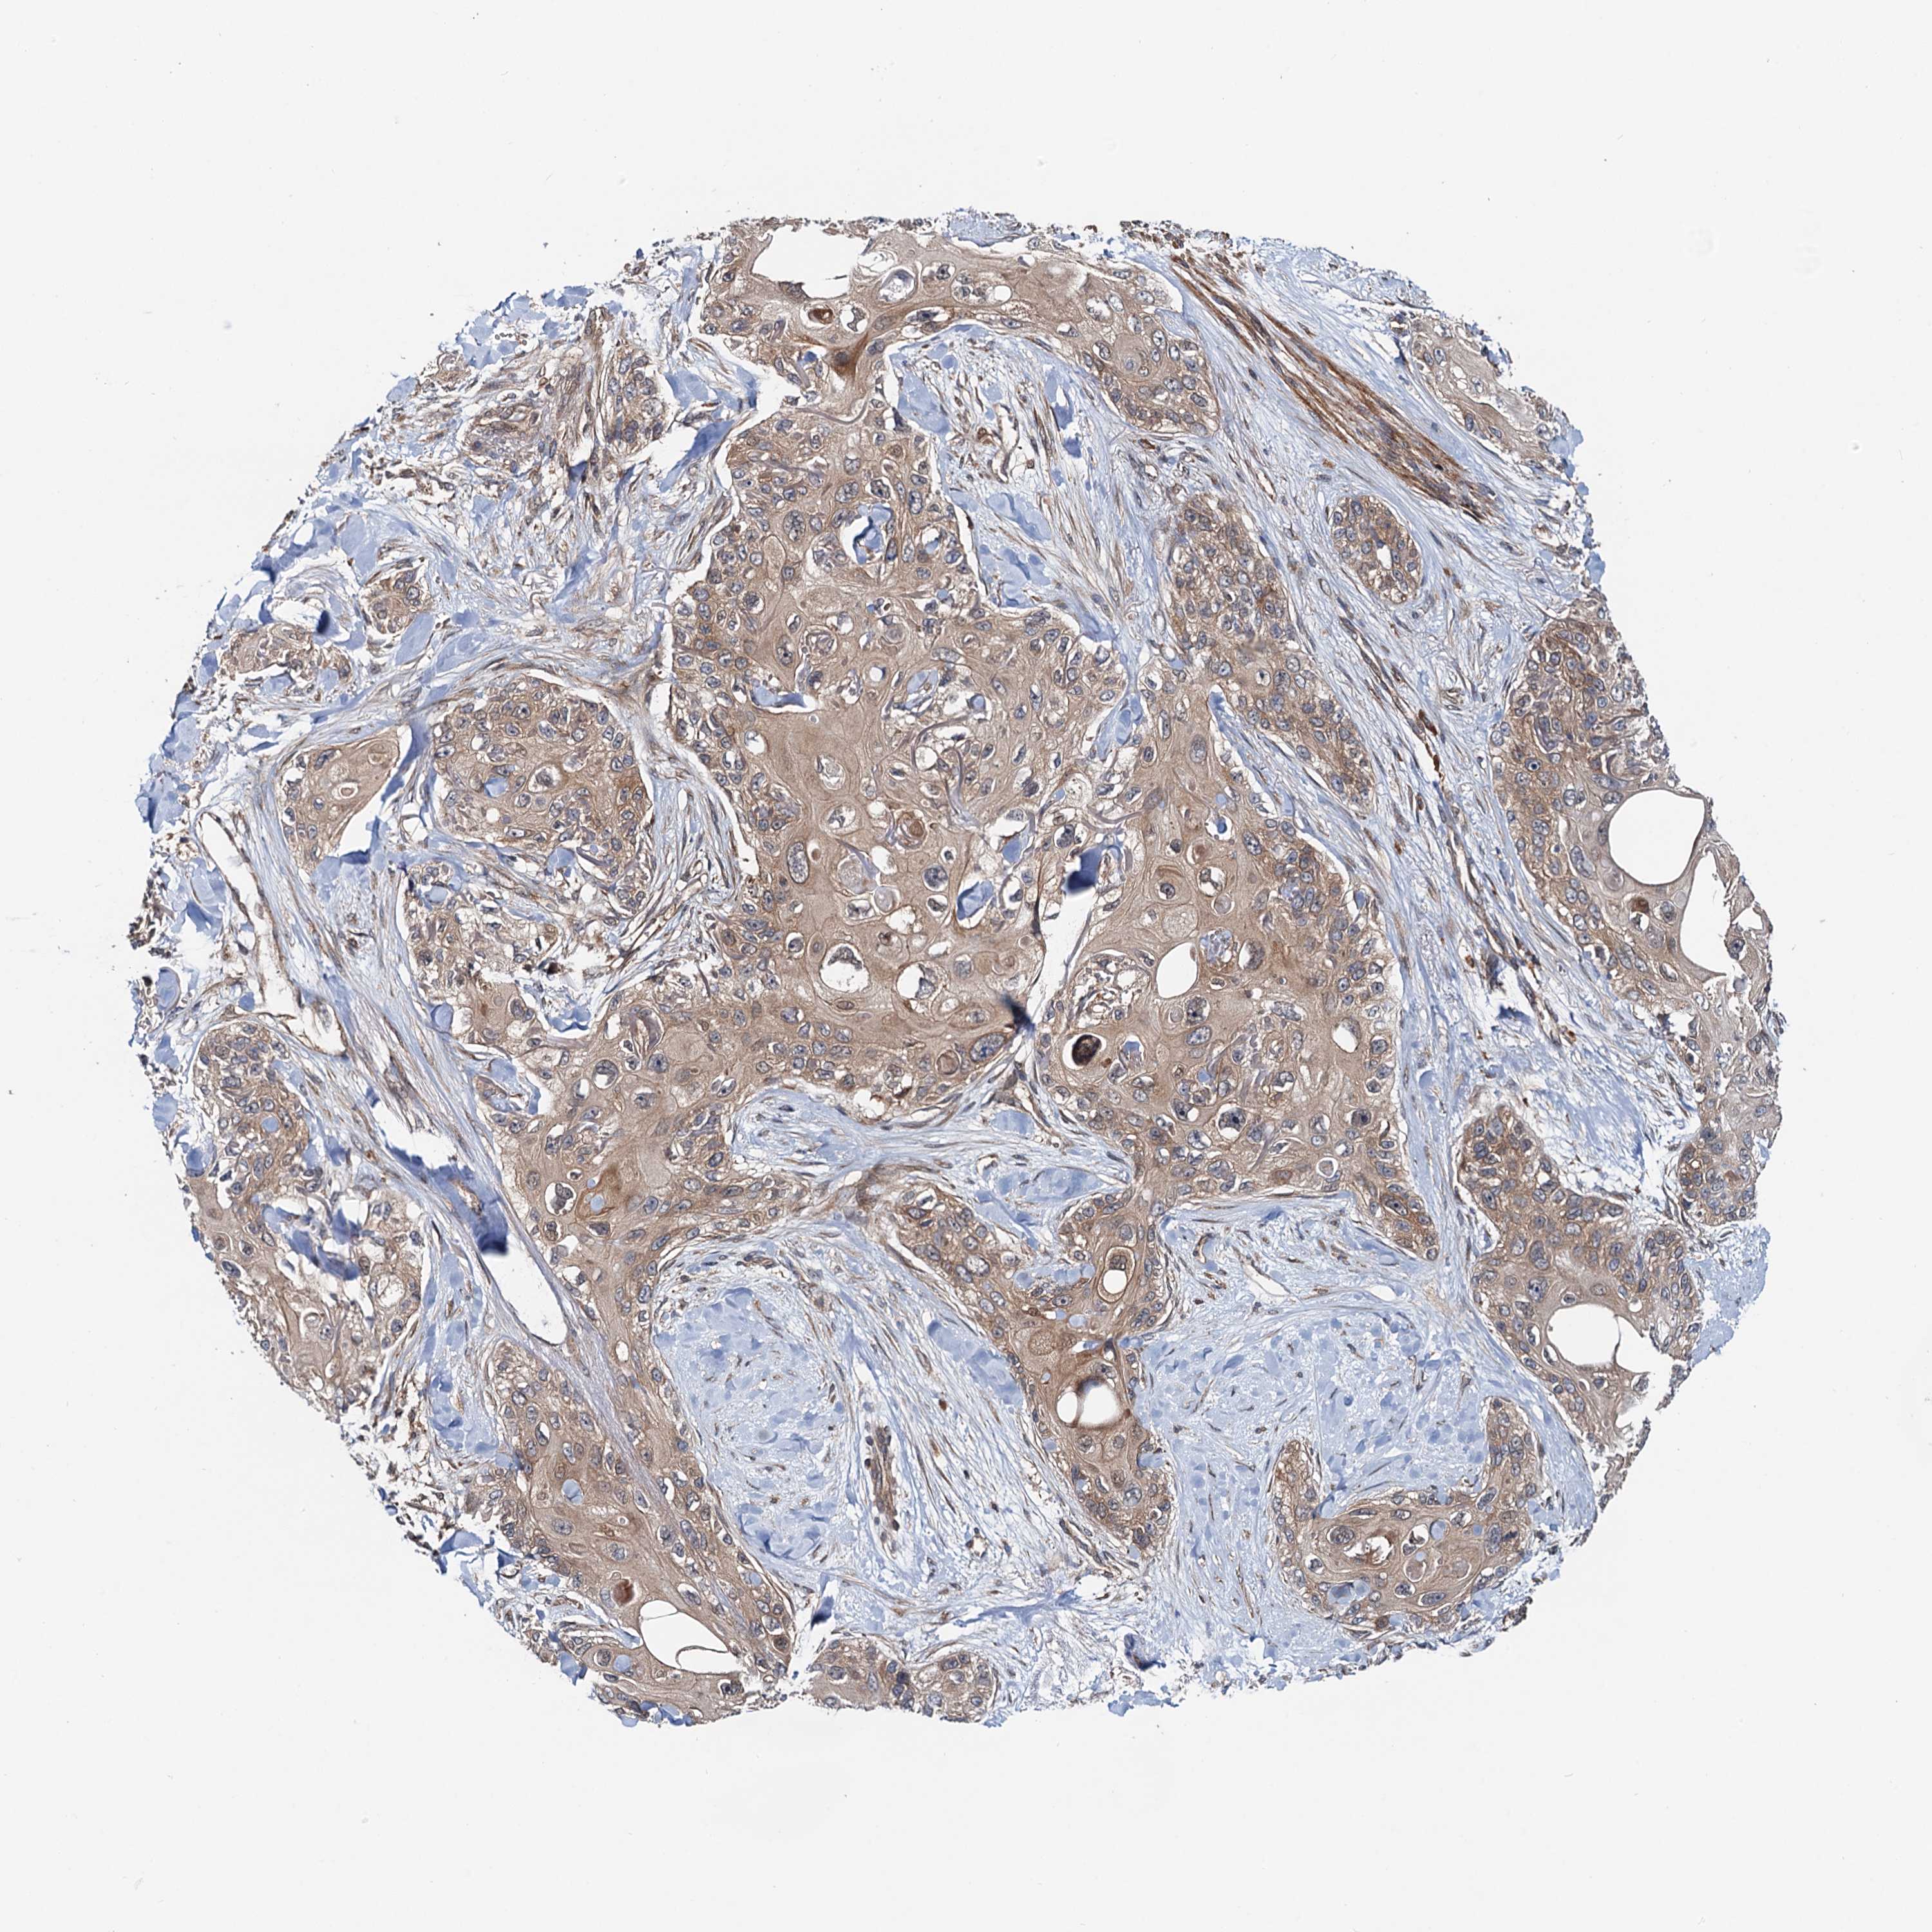

Basal cell and squamous cell cancer

SKIN CANCER - Protein expressioni

A mouse-over function shows sample information and annotation data. Click on an image to view it in a full screen mode. Samples can be filtered based on level of antibody staining by selecting one or several of the following categories: high, medium, low and not detected. The assay and annotation is described here.

Antibody stainingi

Antibody staining in the annotated cell types in the current human tissue is reported as not detected, low, medium, or high, based on conventional immunohistochemistry profiling in selected tissues. This score is based on the combination of the staining intensity and fraction of stained cells.

Each image is clickable and will lead to virtual microscopy that enables deeper exploration of all samples and also displays staining intensity scores, fraction scores and subcellular localization as well as patient and tissue information for each sample.

Antibody HPA039371

Antibody HPA040174

Staining

High

Medium

Low

Not detected

Intensity

Strong

Moderate

Weak

Negative

Quantity

>75%

75%-25%

<25%

None

Location

Nuclear

Cytoplasmic/membranous

Cytoplasmic/membranous,nuclear

Basal cell carcinoma

Squamous cell carcinoma, NOS

Squamous cell carcinoma, metastatic, NOS